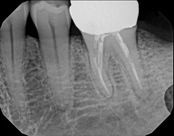

Lower molar failed root canal, microsurgery saved the tooth:

Before

Immediately after

3-month follow-up with complete healingThis patient presented with a failed root canal. The root canal became infected. An apicoectomy (apical microsurgery) was performed using the laser. Patient had minimal swelling, minimal discomfort, and fast healing. The tooth was saved and an implant avoided. This tooth tends to have a lower success rate with root canal therapy; thankfully apical microsurgery was available to save the tooth.

At the 3 month follow-up, the gums look like nothing was done thanks to the skill and use of the laser for the procedure.